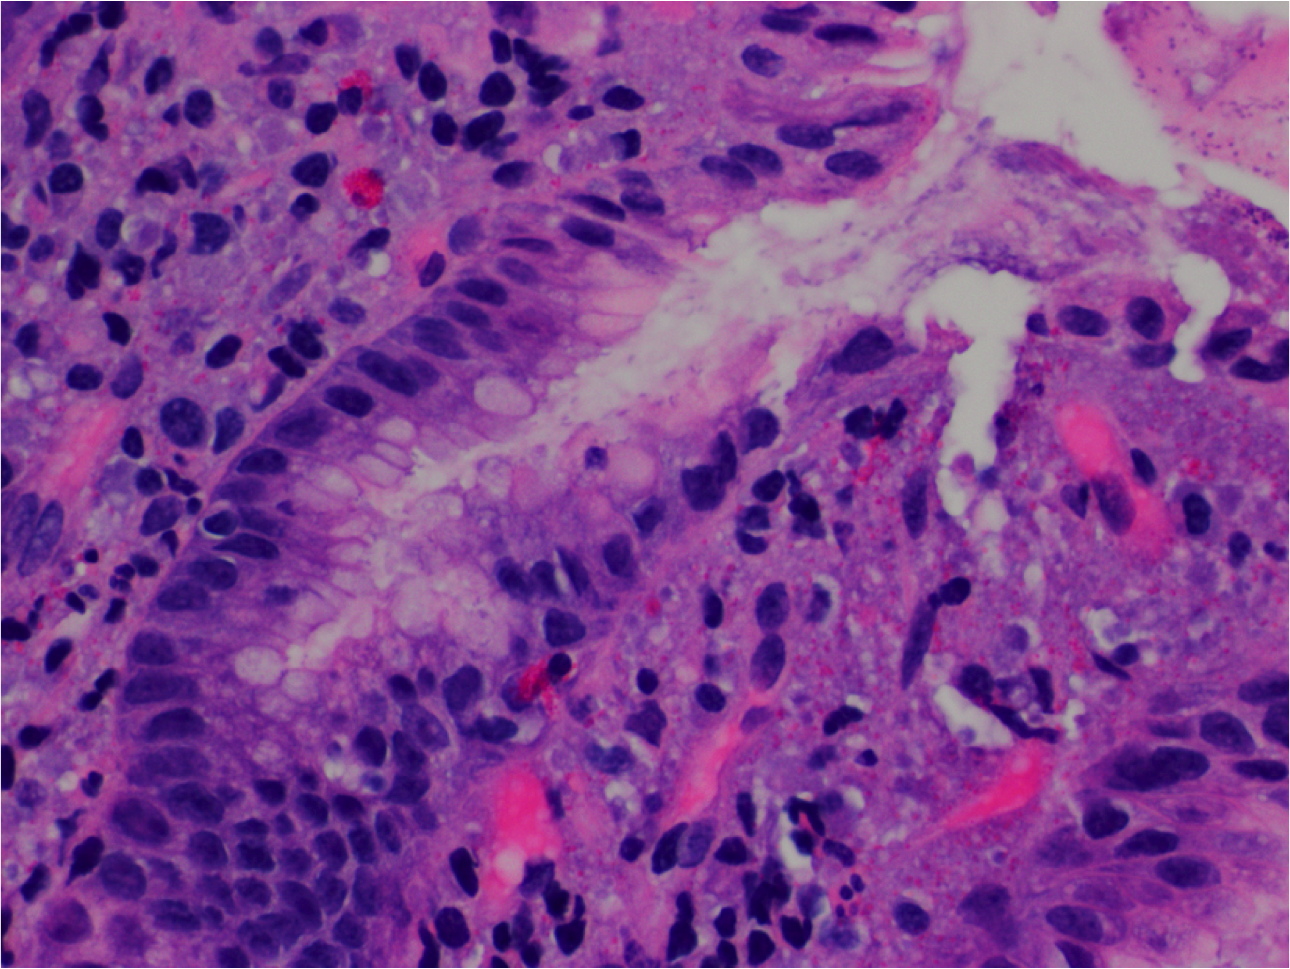

What’s this? Notable?

Adenocarcinoma.

Cribriforming, nuclear pleiomorphism and hyperchromasia, atypical mitoses (middle left).